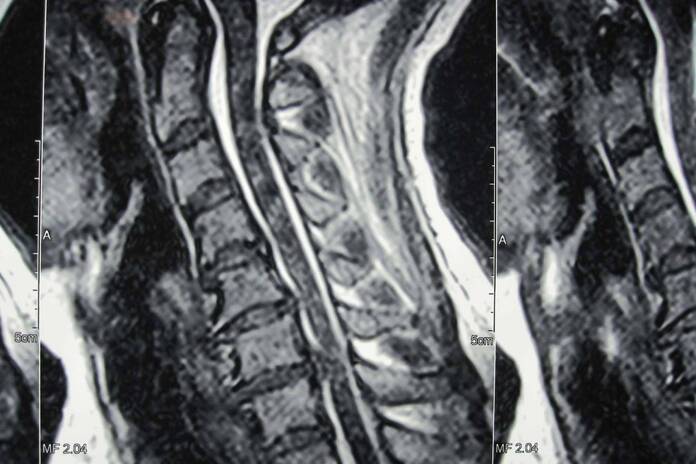

Además de ser un soporte para el tronco, la columna vertebral también es un protector de la médula espinal, así como el punto de unión de las costillas y los músculos de la espalda. Entre cada vértebra de la columna, hay discos cervicales, una especie de amortiguadores naturales para el impacto de las acciones cotidianas, que distribuyen las cargas a las que se expone la columna. Pero, con el paso del tiempo, de manera natural se va degenerando poco a poco, produciendo fisuras que pueden generar diferentes patologías, tales como la hernia discal cervical. Esta se produce cuando uno de los discos intervertebrales degenerados se rompe en algún punto de su circunferencia. Esto causa que su contenido salga y presione un nervio cervical, causando dolor que en los casos avanzados puede llegar a ser muy intenso, limitado el movimiento y afectando la calidad de vida de la persona. Dependiendo de la gravedad del caso, se pueden recurrir desde tratamientos locales no invasivos, hasta cirugías mínimamente invasivas, tales como la artrodesis cervical.

La microdiscectomía cervical es el procedimiento más común y recomendado en caso de una hernia disco cervical. Se trata de un procedimiento poco invasivo que en el caso de realizarse para artoplastia, consiste en la extracción de un disco intervertebral cervical dañado, en este caso, el que provoca la hernia. Este disco es el responsable de provocar los fuertes dolores, presionar la médula y comprimir la raíz nerviosa. La incisión se hace en la zona lateral anterior del cuello para poder tratar el disco dañado sin lesionar las estructuras adyacentes. En la clínica Neurocirugía Galarza, sus profesionales se encargan de estudiar meticulosamente el historial del paciente, el tiempo transcurrido de los síntomas, la magnitud de los mismos y la reacción del paciente a otros tratamientos. De esta manera, se asegura un procedimiento exitoso y efectivo para el paciente, restituyendo su salud y bienestar.